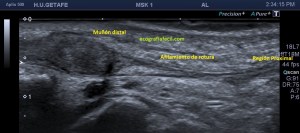

En este breve post te voy a presentar unas imágenes muy bonitas de una vesícula, en una paciente que acude a la cita de ecografía por sospecha de patología a ese nivel, con molestias anodinas e inespecíficas en el contexto de un estudio de su especialista de digestivo.

Observa las imágenes y luego te explico los hallazgos:

Cuando hice el corte longitudinal de la vesícula pude ver hasta tres patologías distintas, una adeomiomatosis (sin artefacto en cola de cometa), una litiasis vesicular y barro biliar, 2,3 y 4 respectivamente.

El caso no tiene mucho que explicar a no ser por la rareza de que se presente triple la semiología patológica en una misma imagen.

La adenomiomatosis, como un aumento de la ecogenicidad y el tamaño de la pared vesicular, la litiasis como una estructura hiperecogénica con sombra acústica posterior y el barro biliar, hiperecogénico rellenando toda la estructura ovoidea de la vesícula.

El cuello vesicular estaría afectado por la adenomiomatosis, el cuerpo por la litiasis y el barro ocuparía el fundas vesicular.

Para el estudio de la adenomiomatosis es obligado que el foco esté situado en la línea de interés, eso hará que las imágenes sean más nítidas y podamos estudiar dicha ecoarquitectura y su patología convenientemente.

Debemos observar si existiese líquido perivesicular, o signos de colecistitis. En este caso, la paciente, con estas tres patologías ya iba bien servida.